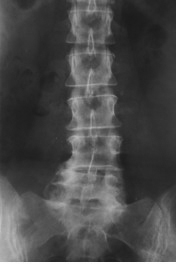

Die weitaus meisten Rückenprobleme sind duch einen relativ früh beginnenden Verschleissprozess der Wirbelsäule bedingt.